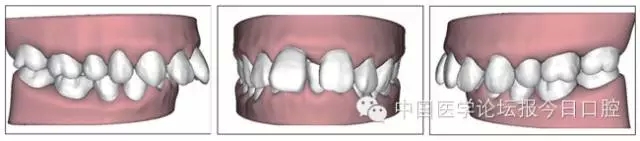

全口曲面體層片(圖3)顯示,患者全牙列牙槽骨吸收;根尖片(圖4)示11近中牙槽骨角形吸收已達根尖1/3,21牙槽骨嵴頂吸收至根1/2,23牙槽骨近中骨板角形吸收至根1/2。磨牙區(qū)骨嵴頂吸收3mm。治療前頭顱側位片見圖3,治療前ODS模型見圖5。

圖5 治療前ODS模型